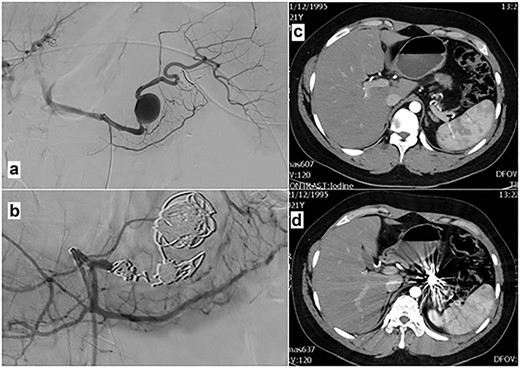

Twelve hours later, the patient complained of diffuse abdominal pain, while a decrease of hemoglobin was observed (9.5 mg/dL), and hemodynamic instability presented, with an increase in heart rate to 100 bpm. He was initially treated with intravenous fluids; surgical opinion was then seeked. Clinical examination revealed pronounced rebound tenderness on all of the abdominal quadrants and decreased abdominal sounds. In order to investigate the possibility of intraperitoneal bleeding and considering the stability of the patient, an emergency abdominal CT scan with i.v. contrast was indicated. CT scan revealed the presence of a ruptured proximal splenic artery aneurysm measuring 26 mm × 18 mm, 6 cm from its origin (Fig. 1).

Abdominal CT scan at the onset of patient’s hemodynamic instability: (a) CT-image before the iv contrast administration shows the aneurysm (arrow) and free fluid (blood) into the infraperitoneal space and peritoneal cavity (arrowhead). (b, c and d) Post contrast CT-images (arterial phase) reveal the ruptured aneurysm clearly the free blood collection into the infraperitoneal space (arrowhead).